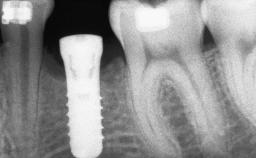

Guided Bone Regeneration (GBR) with a Particulated Autologous Graft and a ePTFE-Reinforced Membrane for Vertical Augmentation of a Single-Tooth Edentulous Space in the Esthetic Zone

# of Implants 1

Type of Implants Two-Piece

Placement Protocol Early or late implant placement

Loading Protocol Conventional or early